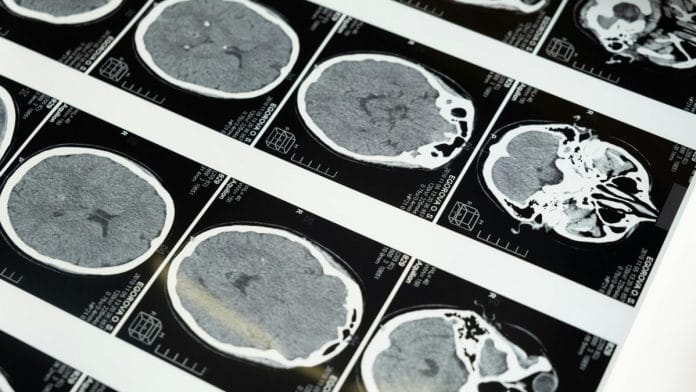

This time is also significant as it is when mental disorders are most likely to take root. The findings of the study could also play a role in determining and tracking the origins of mental illnesses and multiple other neurological disorders.

“Many neurodevelopmental, mental health and neurological conditions are linked to the way the brain is wired. Indeed, differences in brain wiring predict difficulties with attention, language, memory, and a whole host of different behaviours,” Duncan Astle, a professor of neuroinformatics at the University of Cambridge has been quoted as saying by the BBC.